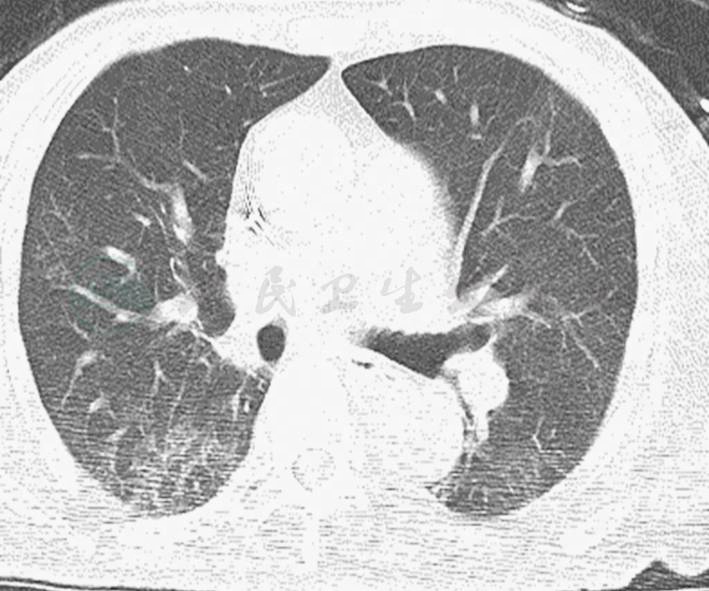

入科查体:T 36.8℃,HR 80次/分(起搏心律),BP 166/60mmHg[多巴胺5μg/(kg·min)持续静脉泵入],RR 24次/分。SPO2 95%(鼻导管吸氧5L/min),神志清楚,半卧位,颈静脉充盈,两肺可闻及干、湿性啰音,心脏听诊未闻及明显杂音,双下肢轻度凹陷性水肿,余未查见明显阳性体征。测CVP 6mmHg;血常规:WBC 13.2×109/L,N 87.3%;血气分析:pH 7.293,PaO2 67mmHg,PCO2 30mmHg,PaO2/FiO2 160mmHg,Lac 3.9mmol/L;BNP 247ng/ml;TnI 1.11ng/ml;PCT阴性。肝功能:ALB 24g/L,ALT 133u/L,AST 84u/L。入科查胸部平片示两肺弥漫性渗出影,以右肺为重(图2)。胸部CT提示右肺肺炎、两下肺支气管扩张伴感染,较上次胸部CT(图1)明显进展;两侧少量胸腔积液、心包少量积液(图5-3)。

4.胸片提示两肺渗出性病变,以右肺为重。胸部CT可见类似结果;BNP轻度升高。